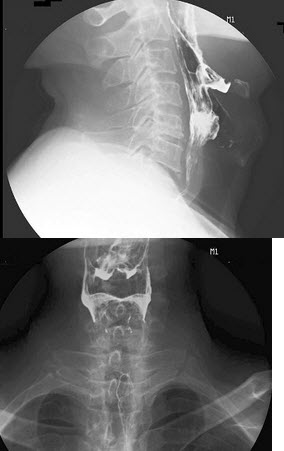

31、单项选择题

女,45岁,咽喉不适,异物感。体检:仅见慢性咽炎改变,结合图像,最可能的诊断为()

A.正常表现

B.会厌征

C.颈椎退变

D.食管型颈椎病

E.以上都不是